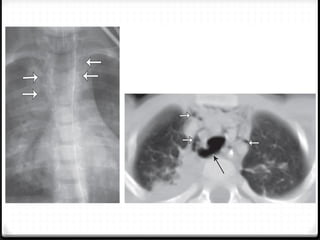

Fraktur costae

0 Most common skeletal injury (± 50%)

0 Simple ribs fracture rare life threatening

0 Multiple  more severe injury  ↑ morbidity & mortality

0 Location of fracture

0 X-ray and CT

 x-ray : limited sensitivity, helpful >>  Oblique >> AP/PA

 CT scan : most sensitivity

2009

Fraktur costae 0 Mostcommon skeletal injury (± 50%) 0 Simple ribs fracture rare life threatening 0 Multiple  more severe injury  ↑ morbidity & mortality 0 Location of fracture 0 X-ray and CT  x-ray : limited sensitivity, helpful >>  Oblique >> AP/PA  CT scan : most sensitivity